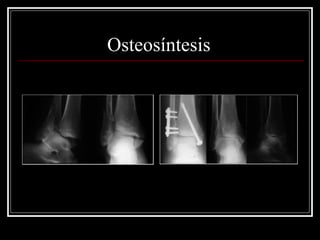

Osteosíntesis